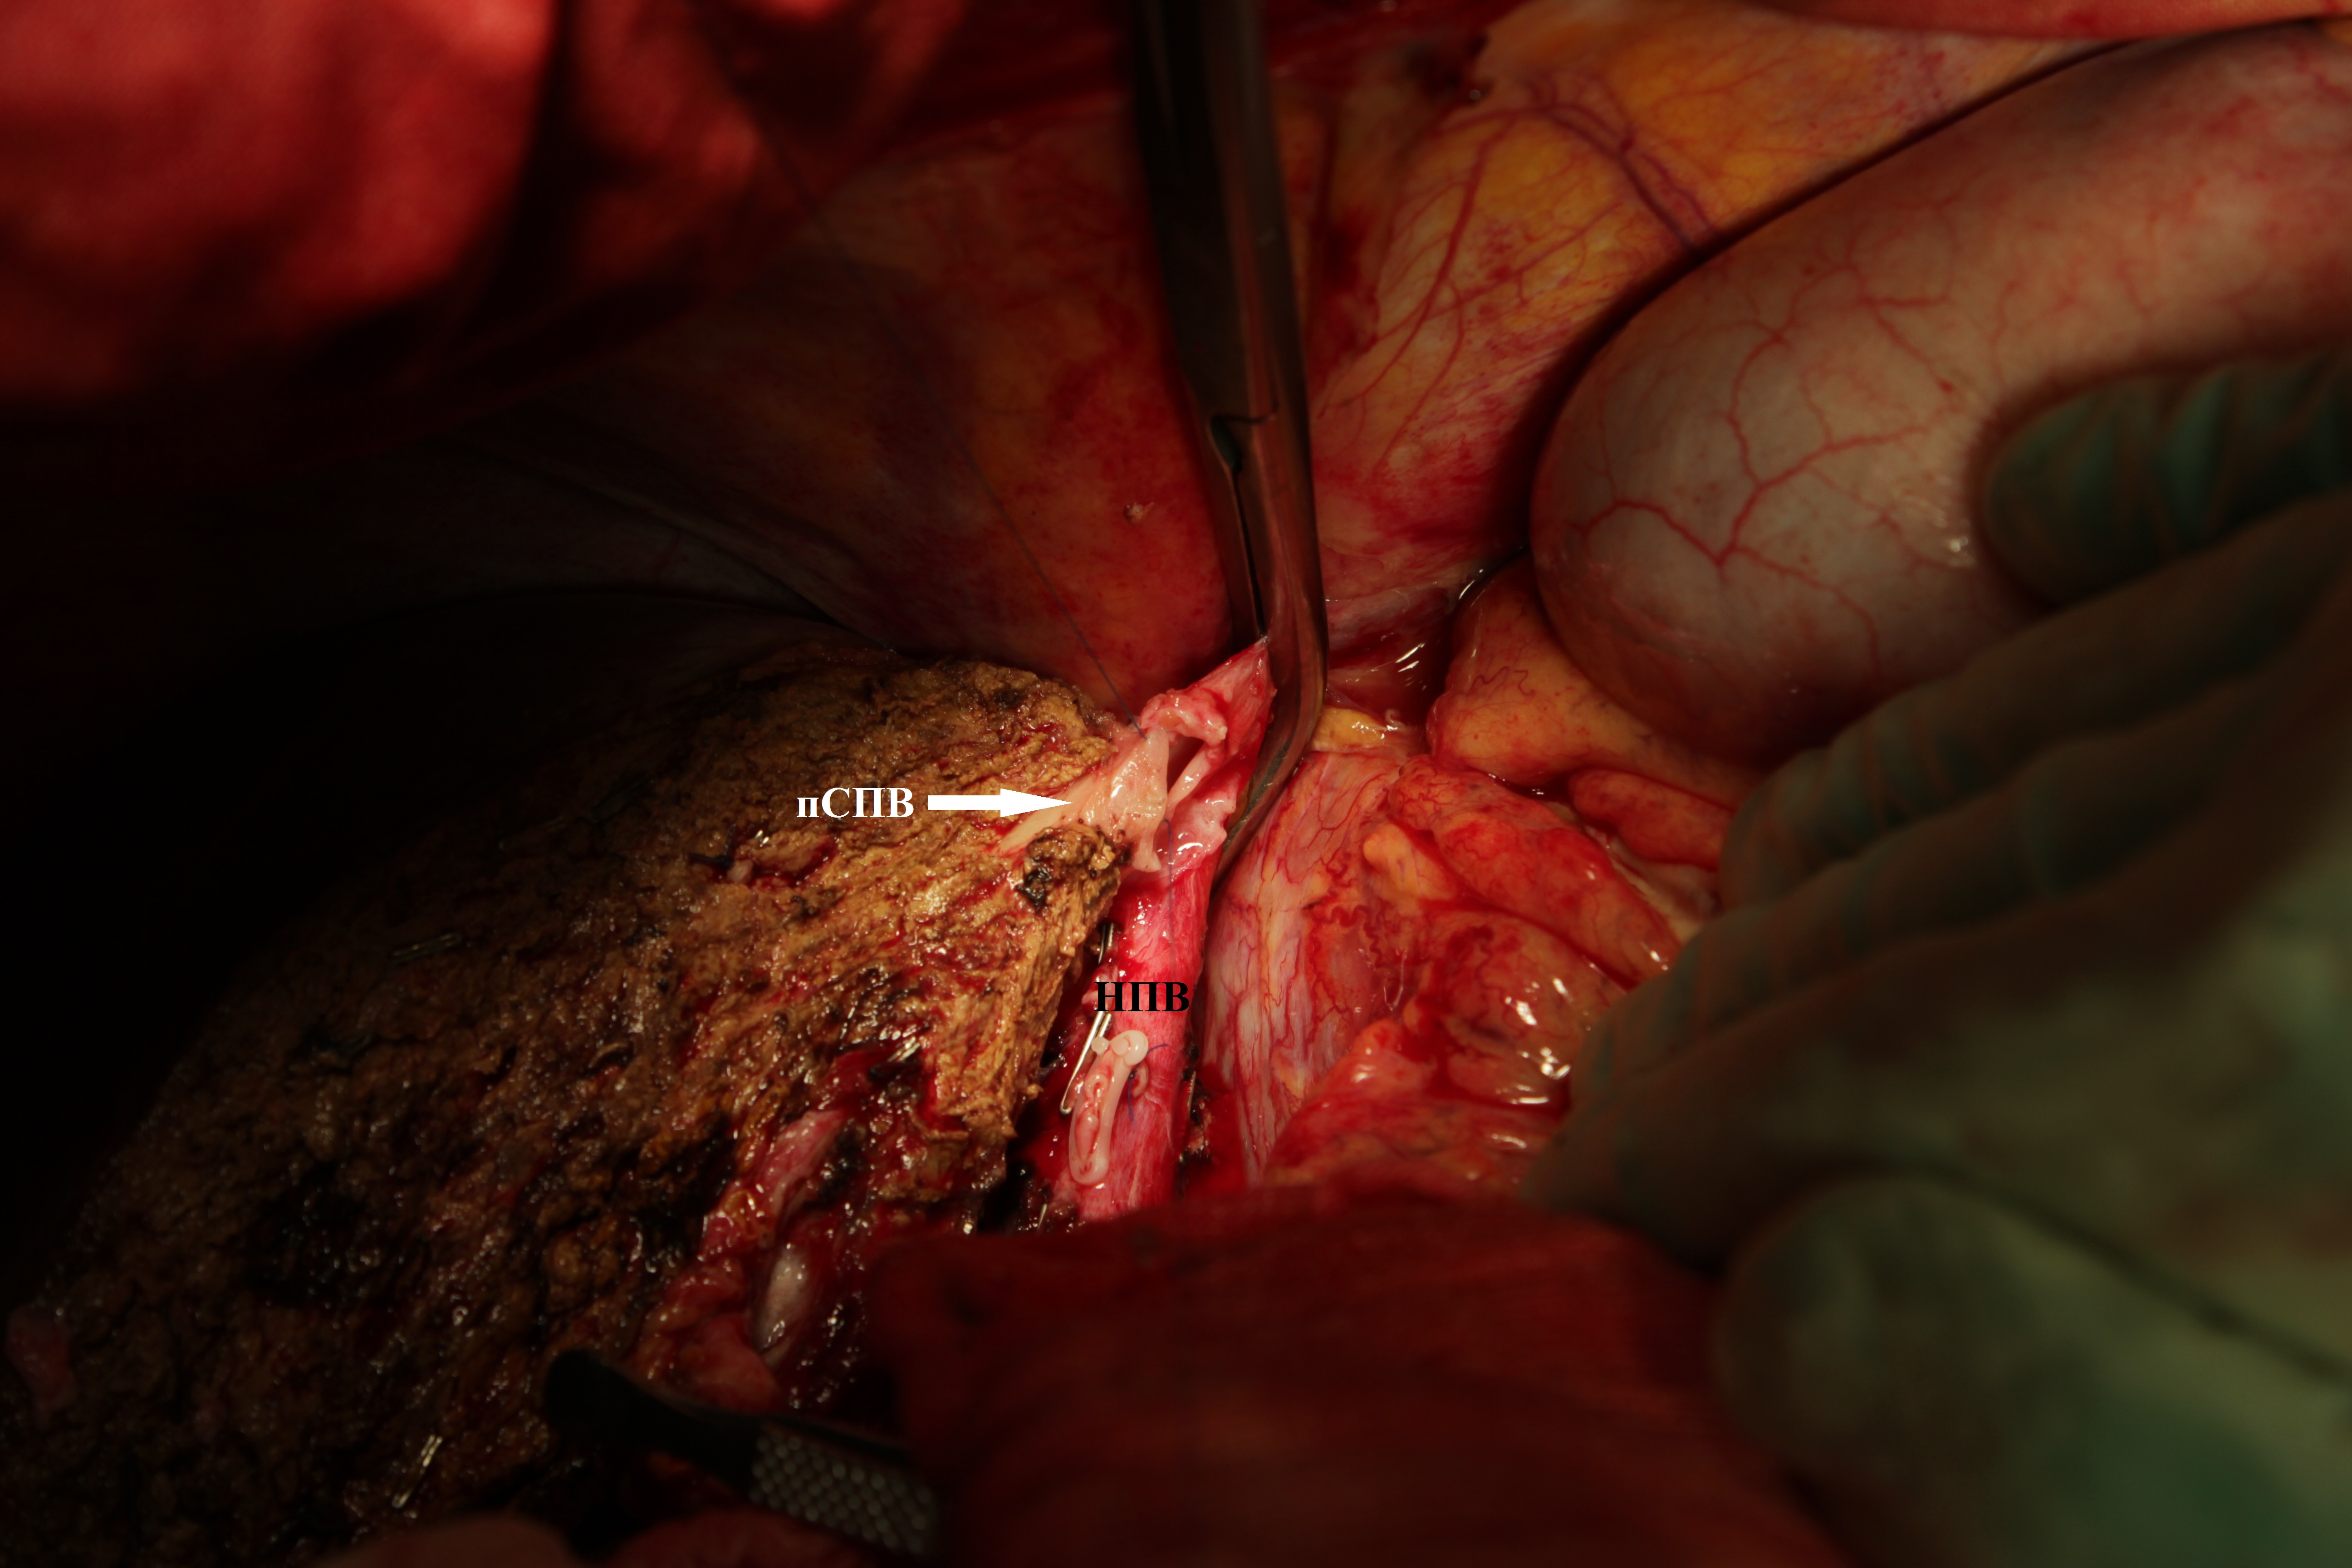

1. Рис. 1а. Позиционирование ППВ и НПВ перед формированием гепатикокавального анастомоза | |